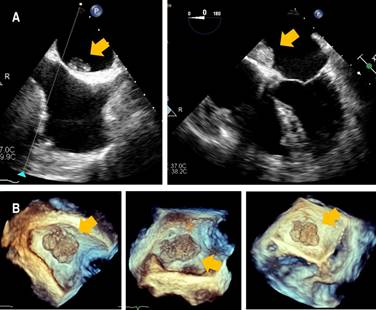

Transesophageal echocardiography revealed a 26 × 16 × 14 mm heterogeneous, lobulated, mobile mass in the left atrium, attached to the interatrial septum, and without obstruction to the flow across the mitral orifice (Figure 2).

Figure 2: Transesophageal echocardiography. A) Heterogeneous, lobulated mass in the left atrium attached to the interatrial septum. B) Real-time 3-dimensional echocardiography (RT3DE ) image.